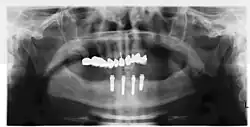

- имплантация All-on-4 («все на 4») — это зубопротезирование полного зубного ряда методом имплантации четырёх искусственных корней (имплантатов) в костную ткань челюсти пациента с последующей установкой на них протеза.

- с помощью рентгенографии изучаются качество и плотность костной ткани;